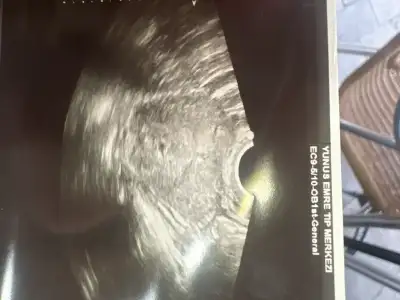

Cok normal daha cok küçük haftaya gittiğinde biraz daha büyümüş olurDoktordan çıktım kızlar daha çok minik doktor karından gözükmez dedi vajinadan baktı haftaya çarşamba tekrar gel dedi

Bebek nerde siyah olan nokta mıDoktordan çıktım kızlar daha çok minik doktor karından gözükmez dedi vajinadan baktı haftaya çarşamba tekrar gel dedi

Ortada siyah olan keseymiş haftaya çarşamba daha iyi gözükür dediBebek nerde siyah olan nokta mı

Bu miniklerin büyüme serüveni çok bekletecek biziiOrtada siyah olan keseymiş haftaya çarşamba daha iyi gözükür dedi